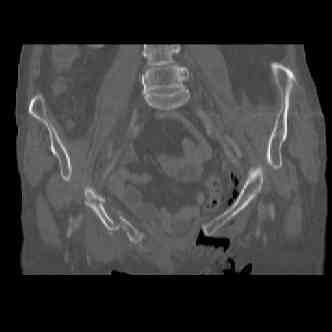

attached are several CT cuts. please let me know if you need more. the CT is pre-pelvic ex-fix placement.

Thank you.

I wouldn't plate the front.

But I would add screws posteriorly.